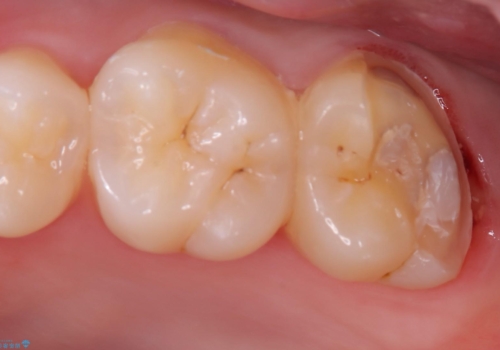

左上一番奥の歯の頬側に実質欠損を伴う虫歯が存在したため、セラミックインレーでの治療となりました。

上顎左側第二大臼歯頬側面から遠心面、咬合面にもう蝕が波及していたためアンレー形態となりました。

清掃しずらい箇所ではあるため、汚れが付きづらい適合性のよいセラミック素材を選択しました。